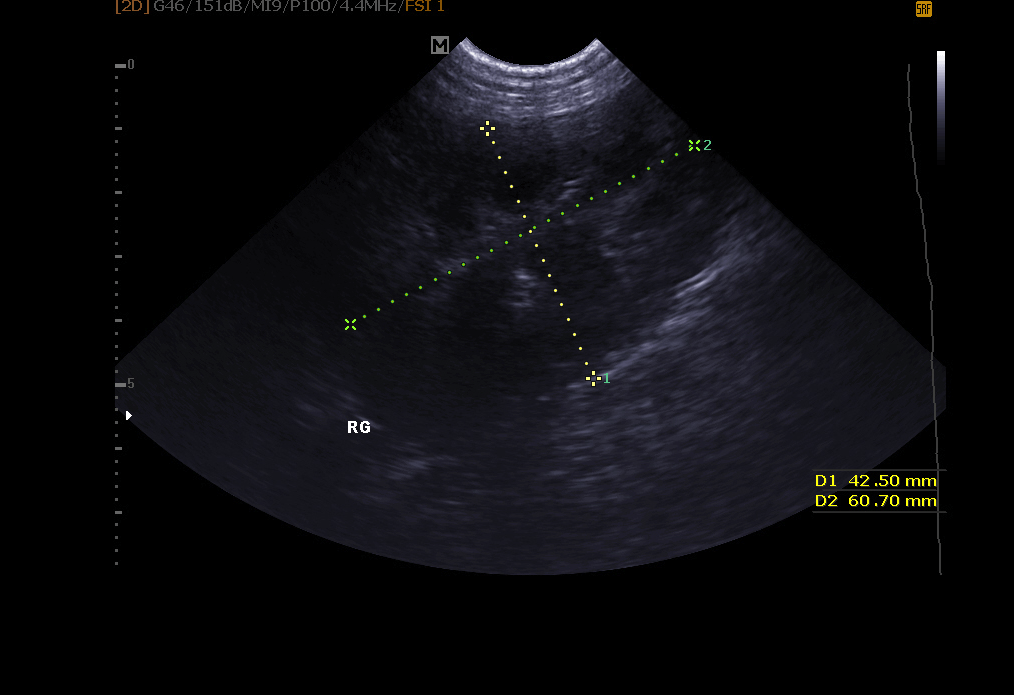

Abdomen-Ultraschall: ermöglicht die Untersuchung der Blase (Suche nach Steinen, Polypen, Tumor), Nieren, Milz, Leber, Bauchspeicheldrüse und anderen Bauchorganen.